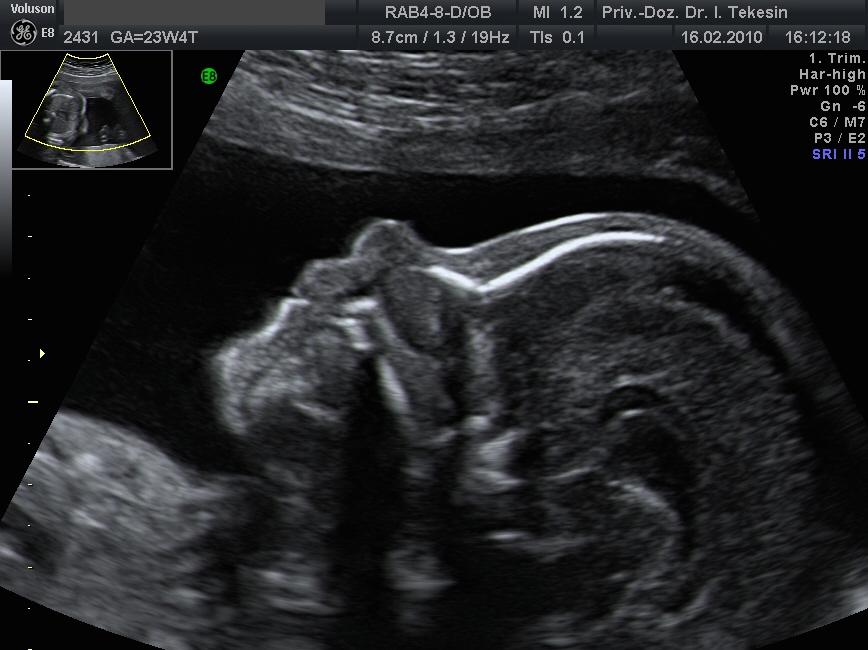

Profil in der 21. Woche

Profil in der 25 Woche